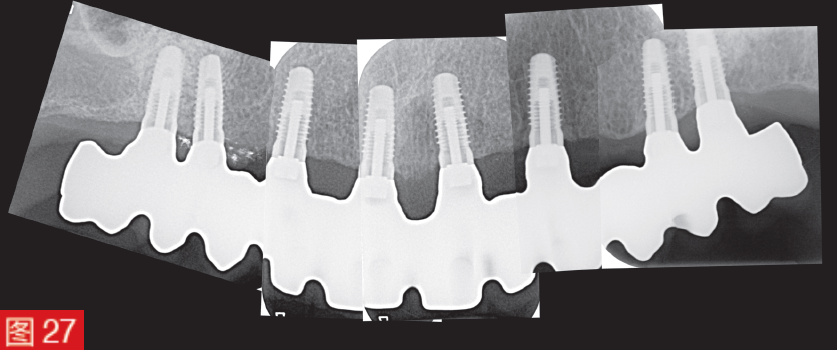

種植體周圍炎的診斷總是與可檢測到的種植體骨吸收有關,當然,最終,影像學研究有助于診斷。因此,在上述情況下,在植入物植入三個月后拍攝了一張令人信服的對照 X 光片。這些 X 光片一方面顯示了植入物和上部結構之間的無縫配合,另一方面顯示了植入物周圍骨骼的良好輪廓,沒有骨骼的水平和垂直塌陷(圖 27)@>。在接下來的幾年中,如果植入物出現問題,這些圖像可以作為重要的參考。

圖 27:植入假體 3 個月后拍攝的 X 光片。